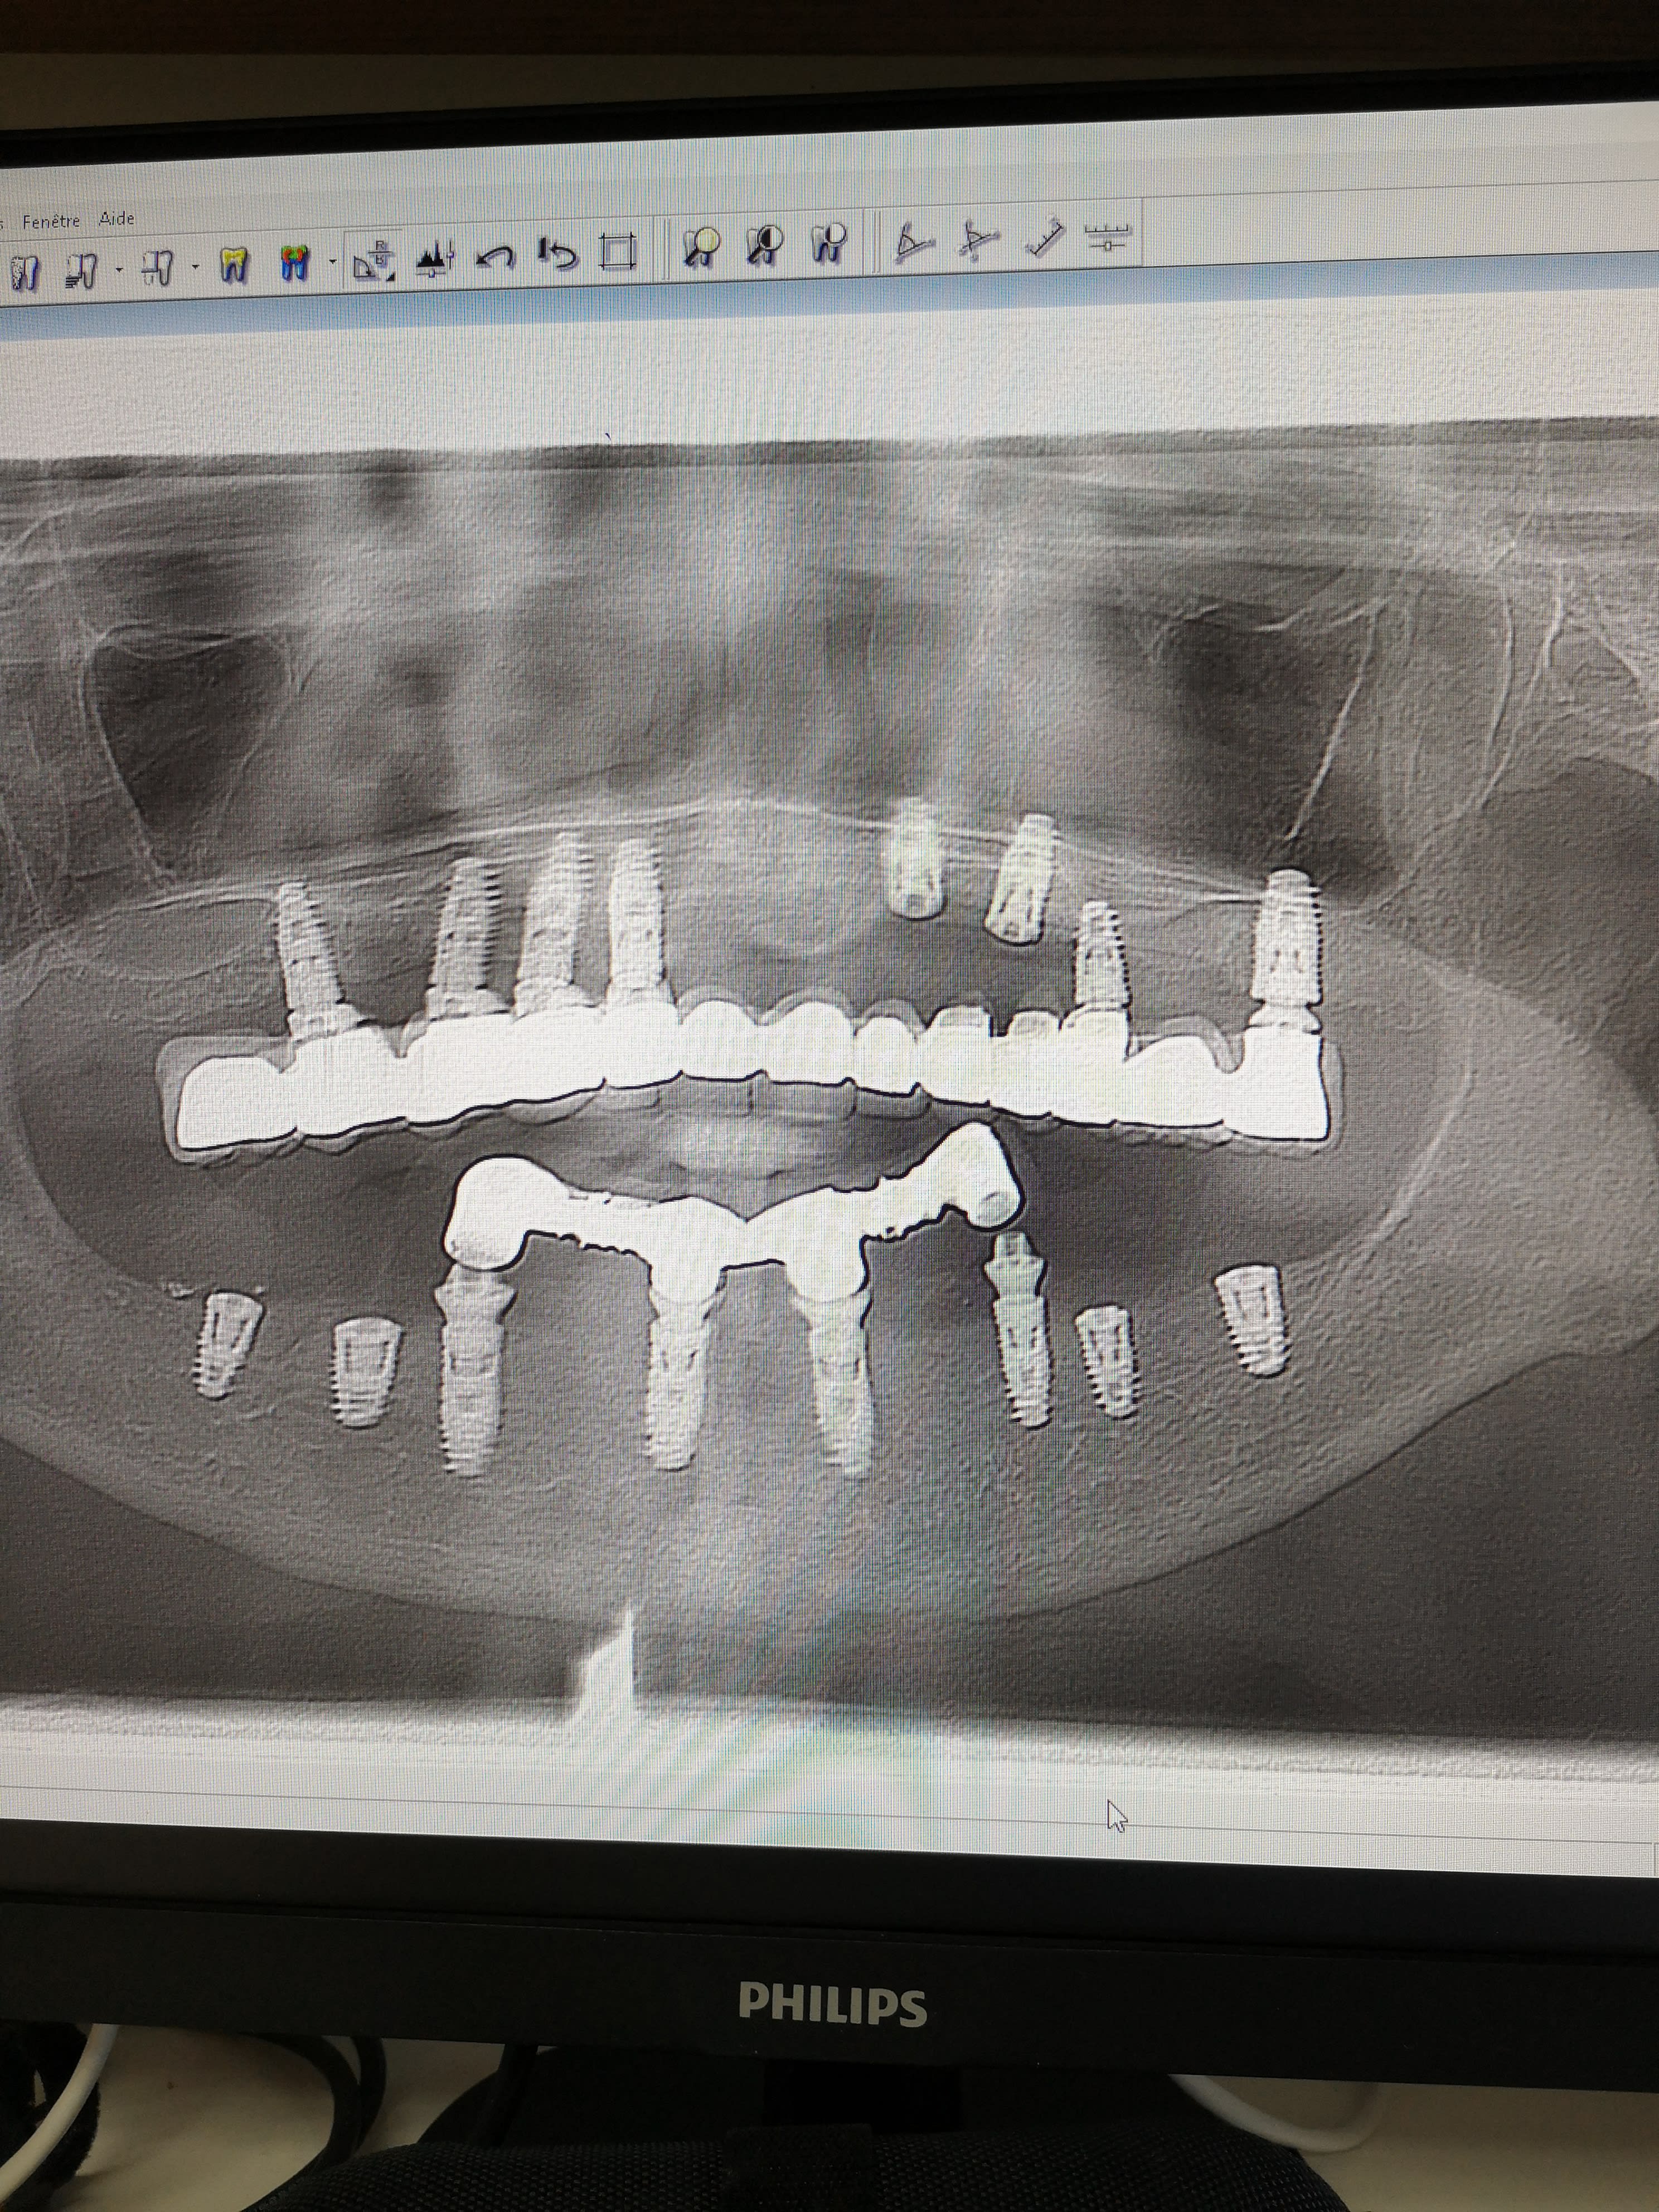

Je dois tout déposer chez cette patiente mais impossible de joindre le poseur.

Quelle marque d'implants selon vous ?

Si tu arrives à savoir ce que c'est avec une image comme ça....

Donc, pour résumer : rétros pour avoir un max de détails sur ces implants et pas en photos d'écran fait avec le smartphone hein ?

Et franchement moi de prime abord j'aurais plutôt pensé à du inkone global D ou du kontact biotech

Je pense aussi au kontact de biotech, tu comptes vraiment tout déposer? Certains implants ont l’air tout à fait exploitables, surtout à la mandibule

J'ai revu la patiente, en pièce jointe les implants.

J'ai l'impression que deux types d'implants ont été posés.

bon et bien là on est fixé, c'est des kontact biotech

http://osseosource.com/dental-implants/product_info.php?manufacturers_id=144&amp;products_id=2524